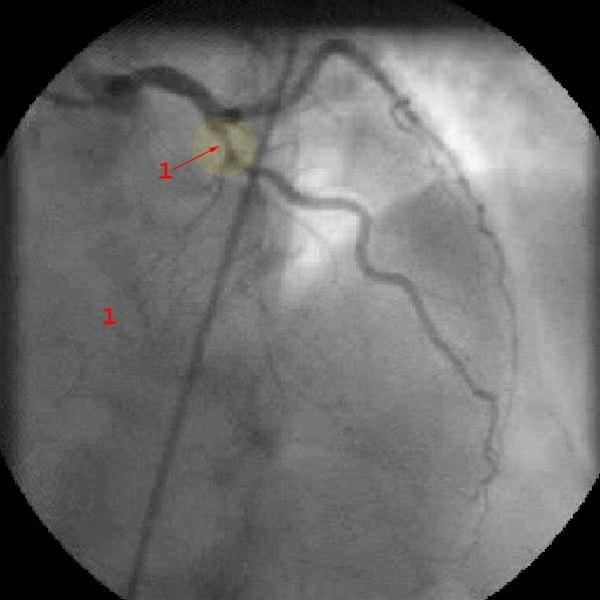

Diagnosen bygger i all hovedsak på sykehistorien. Det vil si de symptomer og tegn som du selv merker. Ved raskt økende brystsmerter av den beskrevne typen bør du ta kontakt med lege snarest. Som regel vil det være aktuelt å legge deg inn på sykehus til observasjon og behandling. EKG og blodprøver vil avklare om det er angina eller om det er oppstått et akutt hjerteinfarkt. I de fleste tilfeller vil det være aktuelt å ta bilder av koronararteriene ved en hjertekateterisering (se video nedenfor).

Tidlig etter innkomsten vil legene vurdere om du bør få utført utblokking av koronararterien(e) som er blitt trange - inngrepet kalles perkutan koronar intervensjon (PCI). Helst vil man gjøre det innen 12-24 timer.

Ved PCI føres et kateter inn i den trange blodåren, åren vides ut og i de fleste tilfeller setter man inn en stent. Stent er en type armering som skal forebygge at blodåren lukker seg igjen. Andre ganger kan det bli nødvendig med en åpen hjerteoperasjon der man syr inn en ny blodåre forbi den eller de årene som er trange (bypass-operasjon).